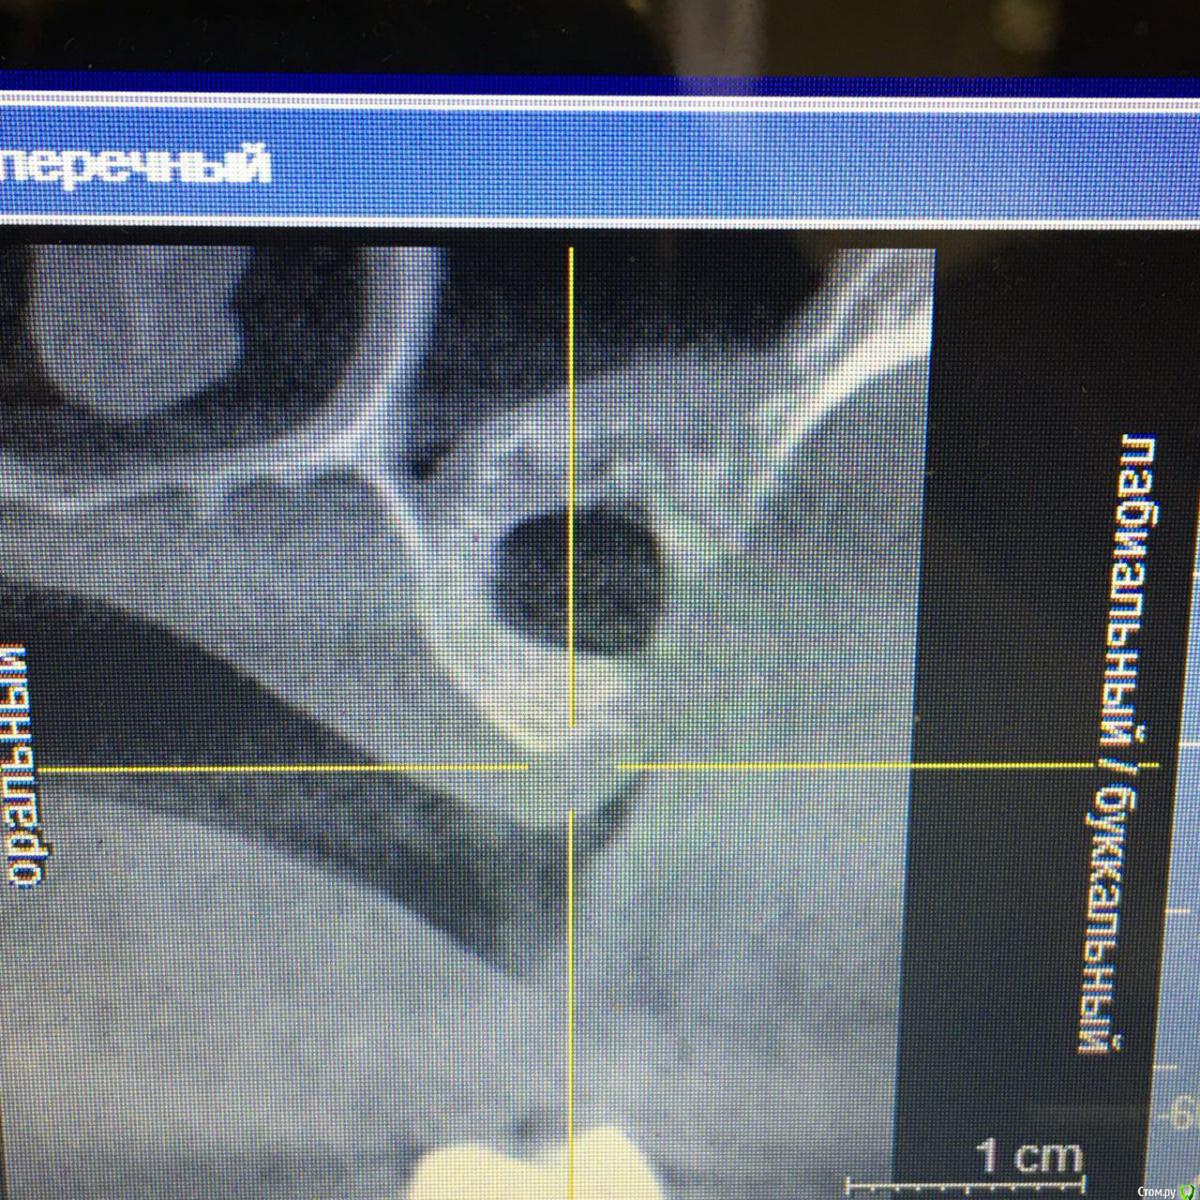

Andre_ Опубликовано 6 сентября, 2018 Автор Поделиться Опубликовано 6 сентября, 2018 Продолжение истории. Во время моего отпуска пациентка с жалобами на боли в зоне интереса попала в ЧЛХ с диагнозом остеомиелит в/челюсти. Где, со слов пациентки, был убран инкапсулировавшийся инфицированный графт, доступом изо рта ( видимо, с остатками пострадавшего альвеоляра, и вероятно перфорнувшись в пазуху). КТ на момент поступления прикладываю. В настоящий момент п/о рана во рту заживает вторично. Пока что пациентка получила частично средства за манипуляции и обещала явиться на КТ контроль. Думаю направить позже ЛОРам, если что. И придумывать НКР + винты. 2 Ссылка на комментарий